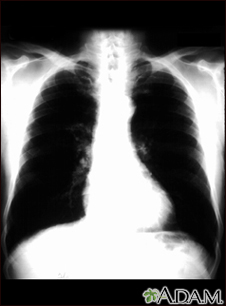

Bronchial cancer - chest x-rayBackBronchial cancer - chest x-rayThis is a chest x-ray of a person with bronchial cancer. This is a front view. The lungs are the two dark areas. The heart and other structures are white areas visible in the middle of the chest. The light areas that appear as subtle branches extending from the center into the lungs are cancerous. E-mail FormEmail ResultsName:Email address:Recipients Name:Recipients address:Message: